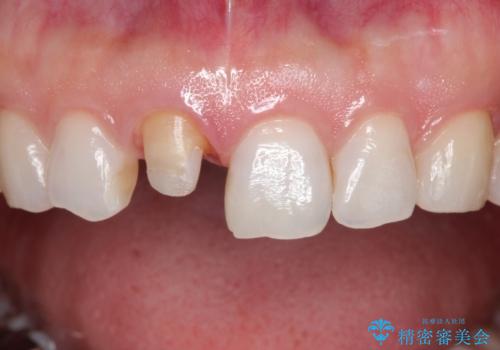

- 「他院で治療した前歯の被せものが一か月の間に2回外れたのでやり変えたい」を主訴に来院されました。

10年前に根管治療を他院で行っており、根尖性歯周炎の予防のため根管治療から行いました。被せものはオールセラミッククラウンで治療を行いました。

10年前にラバーダムシート無しに根管治療を行っており、現在、症状は出ていませんが、根尖性歯周炎の予防のため根管治療から行いました。ホームホワイトニングを2週間行って頂き、その後、オールセラミッククラウンで治療を行っています。

※ファイバーコアとは、根管治療後、歯に立てる土台の事です。金属の土台と比べ歯根破折のリスクが低く、白いのが特徴です。